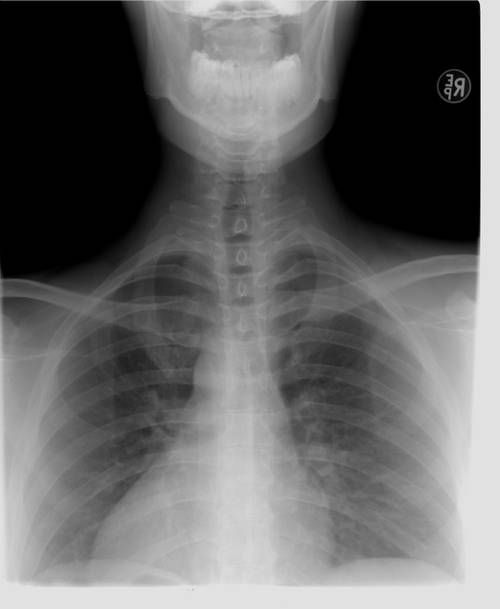

Фото: по лицензии PxHere

Рентген безопасный и полезный

Электромагнитные волны — явление естественное и в определенном количестве незаметное для организма. Доказано, что получить лучевую болезнь удастся тому, кто не менее 5 миллионов раз пройдет рентгенографию грудной клетки. Для этого он должен 4,5 тысяч лет трижды в сутки посещать кабинет рентгенолога.

Избежать облучения репродуктивной системы позволяет специальный фартук. Если снимок делают ребенку, защищают все тело, кроме интересующего участка. Будущим мамам назначают такое обследование только в исключительных случаях.